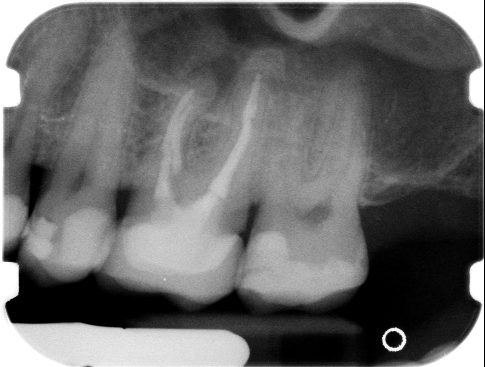

Salve, dopo aver letto molti consigli sui forum e aver effettuato 23 visite alla ricerca di un buon specialista mi trovo ancora nel dubbio su come risolvere il mio problema. I fatti sono questi: 3 anni fa ho devitalizzato e incapsulato 2 molari con corone in zirconio ceramica. Nel primo anno ho avvertito dei fastidi ma sembrava fossero dovuti solo a un precontatto che era migliorato con un leggero molaggio della capsula. Dopo 1 anno in concomitanza con un rifacimento di otturazione di un molare adiacente sono tornati i sintomi di malocclusione con fastidi vari a livello posturale e le cose non sono cambiate nemmeno con una placca in resina da tenere di notte(credo sia una placca per bruxismo e quindi non per terapia gnatologica). Negli ultimi mesi ho effettuato altre visite e dalle Lastrine sembra ci siano dei granulomi periapicale ai denti trattati. Premesso che un dentista mi ha consigliato di effettuare 2 apicectomie e poi terapia gnatologica, mentre un altro mi ha detto che interverrebbe in via ortograda forando la capsula e poi chiudendo la corona come un dente normale(tra l'altro mi ha fatto capire che i granulomi potrei anche lasciarli li se non ci sono complicanze) voi cosa mi consigliate? Altro dubbio, è possibile che i precontatti delle capsule siano stati provocati dal granuloma che ha "spinto" la corona? Grazie di cuore a chi vorrà darmi un consiglio visto che purtroppo non ho trovato molta "condivisione" di vedute tra i dottori che mi hanno visitato e non vorrei correre il rischio di intraprendere cure errate.

Gentile Luigi, i granulomi sono di solito espressione della presenza di infezione all'interno del dente che attraverso la radice raggiunge il tessuto periodontale formando così il granuloma. Nel suo caso le soluzioni proposte sono entrambe valide: provare un ritrattamento forando la corona in ceramica oppure in alternativa procedere alla chirurgia retrograda. Ovviamente la riuscita di una o l'altra metodica dipende molto dalla capacità e professionalità dell'operatore. Pertanto le consiglio di avvalersi dell'opera di un valido professionista senza guardare al lato economico perchè di solito il prezzo stracciato o comunque troppo basso è sinonimo di scarsissima qualità. Cordialmente

Il granuloma purtroppo è presente e va trattato, o per via ortograda o per via retrograda: entrambe le strade sono corrette, in questo caso, nelle mani giuste. Alla lunga, se non trattato (dato che é presente nel contesto di una cura endodontica non congrua) si espanderà e potrebbe portare ad una seria compromissione della stabilità del dente, dell'osso alveolare peri - apicale e a sviluppare un quadro sintomatologico più importante. Questa é l'unica cosa che posso dirle (il pre - contatto non dovrebbe essere correlato al granuloma - estrusione dentale, data l'esiguità della lesione). Si affidi ad uno Studio Dentistico che le trasmette fiducia, senza perdere altro tempo.